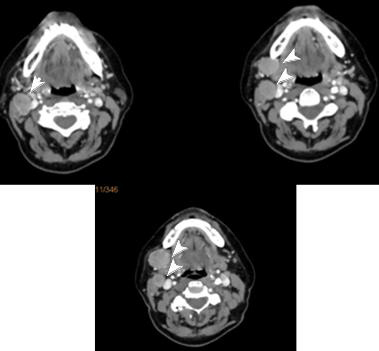

The patient continued with another 3 courses of Ch. In August 2021, the control PET/CT reported a partial metabolic and morphological response from the tracked lymph node in an IB right-cervical level. Presence of metabolic active hyleric and mediastinal lymph nodes, with slightly increased activity in part of the mediastinal nodules, against the backdrop of missing substantial morphological dynamics (Figure 5). The control restaging CT in November takes into account the increase in the right metastatic submandibular lymph node (Figure 6). A second reexcision of the metastatic lymph node was carried out with dissection of deep right cervical lymph nodes. The patient was targeted for post-operative radiotherapy (RT), which was performed with VMAT technique in the field of right-handed cervical lymph nodes from IA to IV level with daily dose (DD) 3 Gy up to total dose (TD) 42 Gy / biologically equivalent dose (BED) 50.4 Gy (Figure 7). After completing the RT, the patient is targeted for immunotherapy.

Figure 5: Control PET/CT (August 2021) - a partial metabolic and morphological response from the tracked lymph node in an IB right-cervical level. Percession of metabolic active hyleric and mediastinal lymph nodes, with slightly increased activity in part of the mediastinal nodules, against the backdrop of missing substantial morphological dynamics.

Complex treatment- A wide local excision with negative margins over 2,5 cm. and sentinel node (SLN) biopsy, is the recommended treatment of choice [52-54]. However, no consensus has been reached with regard to the width of the negative resection margins. There are authors who prove that the wider surgical resection line does not significantly increase the survival. [55]. When comparing pathohistologically positive resection lines with clean resection lines, the following therapeutic results are reported: local recurrences 33.3% / 9.09% (p = 0.19), regional recurrences 66.6% / 27.2% (p = 0.08) and distant metastases 66.6% /45.4% (p = 0.36) [56]. Performing a wide surgical resection is hampered in the head and neck MCC and in the elderly patients with adverse diseases incompatible with general anesthesia [57]. In tumor localization on the face, a sparing operation with a clean resection line of at least 1.5 cm, and MCC on the limbs - 3 cm, is recommended. Radiation therapy was highly effective when given as consolidation after surgery or chemotherapy [58,59]. For reduction of local recurrences, adjuvant RT is required [7,52]. In order to avoid large volume of surgery, initial RT has recommended after the primary tumor excision biopsy as well as prophylactic regional lymph nodes RT [60]. There is a significant reduction in the local (p <0.001) and regional recurrences (p <0.001) when comparing patients after surgery and adjuvant RT with those after a definitive RT. In both groups of patients reported similar results in terms of distant metastases (p = 0.31) [61]. In the clinical case presented, the adjuvant RT is only administered after metastatic lymphatic progression (Figure 5 & Figure 6) and after lymph node reoperation. The volume of post-operative RT should include regional lymph nodes [8,10]. As with the clinical case presented, the postoperative RT of regional lymph metastases is generally passed (Figure 7). The adjuvant RT improves regional tumor control and is a major factor for significantly improved disease-free survival [20,21]. Patients after surgery and adjuvant RT reported significantly higher disease-free survival compared to those after surgery - 23 months against 6 months (p <0.01). The оveral and disease-free survival of the third year reaches respectively 66% and 25% [22]. Until 2017, patients with advanced disease were typically treated with conventional chemotherapies, with a median response duration of 3 months. When used in a first-line setting, PD-1/PD-L1 inhibitors (avelumab, pembrolizumab, nivolumab) are even more promising as objective responses are observed in approximately 50-70% of patients within the first 4-8 weeks of treatment [62]. First line therapy with the PD-L1 blocking antibody avelumab is associated with a response rate of 62% [63]. Treatment with checkpoint inhibitors (CPIs) has shown a major advancement in the treatment of advanced MCC [46].